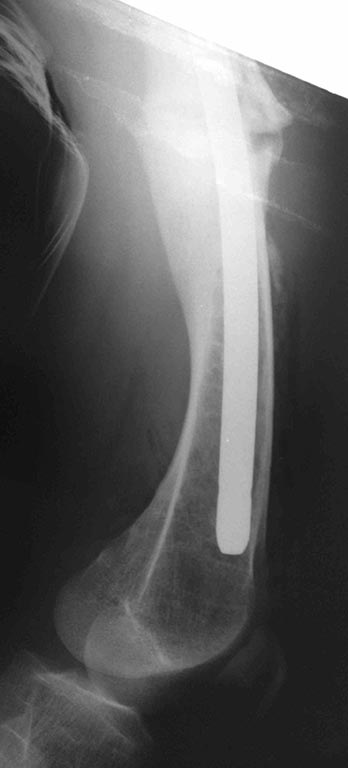

Сегодняшние снимки из операционной, подходящей пластины не было, а гвоздь был.

Stryker S2 длина 280мм, диаметр 12мм

Stryker s2 универсальный,custom made,диаметр 12, не канюлированный.